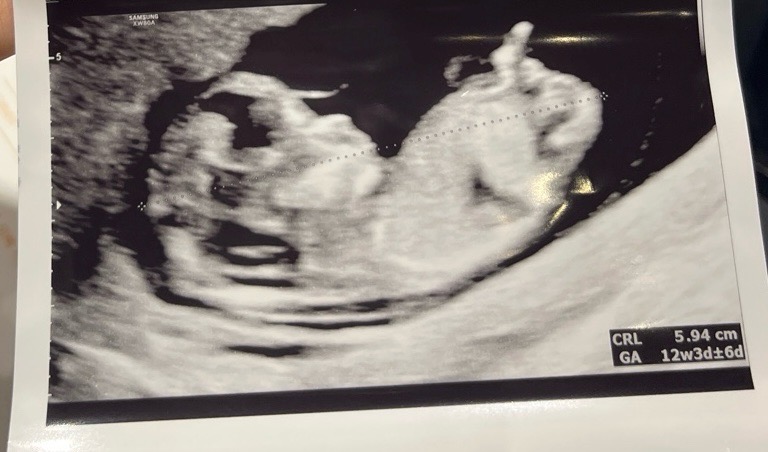

12주 각도법으로 봐주세요ㅠㅠ

아들 일까요 딸 일까요? 중간에 탯줄이예요

아들아닐까용 엉덩이위치가 위로 쏘옥 올라가잇으면 아들이라던댕..ㅎㅎ